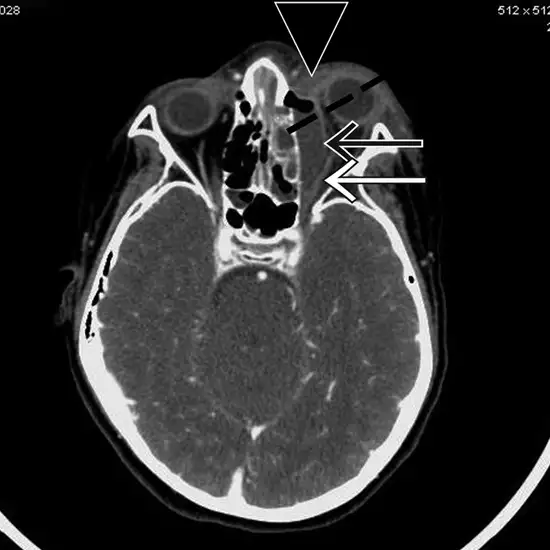

CECT Orbit Axial is an imaging scan that is used to evaluate the orbits, eyes, and their surrounding tissues at the axial plain. It obtains the cross-sectional images of orbit, eye sockets, and eyes to find out the issues/disorders. Doctors recommend this scan to identify the fracture, inflammation, foreign objects in the eye, and eye orbit. Before the scan, the radiologist will inject you with a contrast medium.

CECT Orbit Axial is a diagnostic modality that is used for the examination of the eyes, orbits, and their associated tissues in the axial plain. This scan collects pictures of the orbit and structures in the cross-sectional form. These images are used to determine issues/disorders of your orbit and structures.